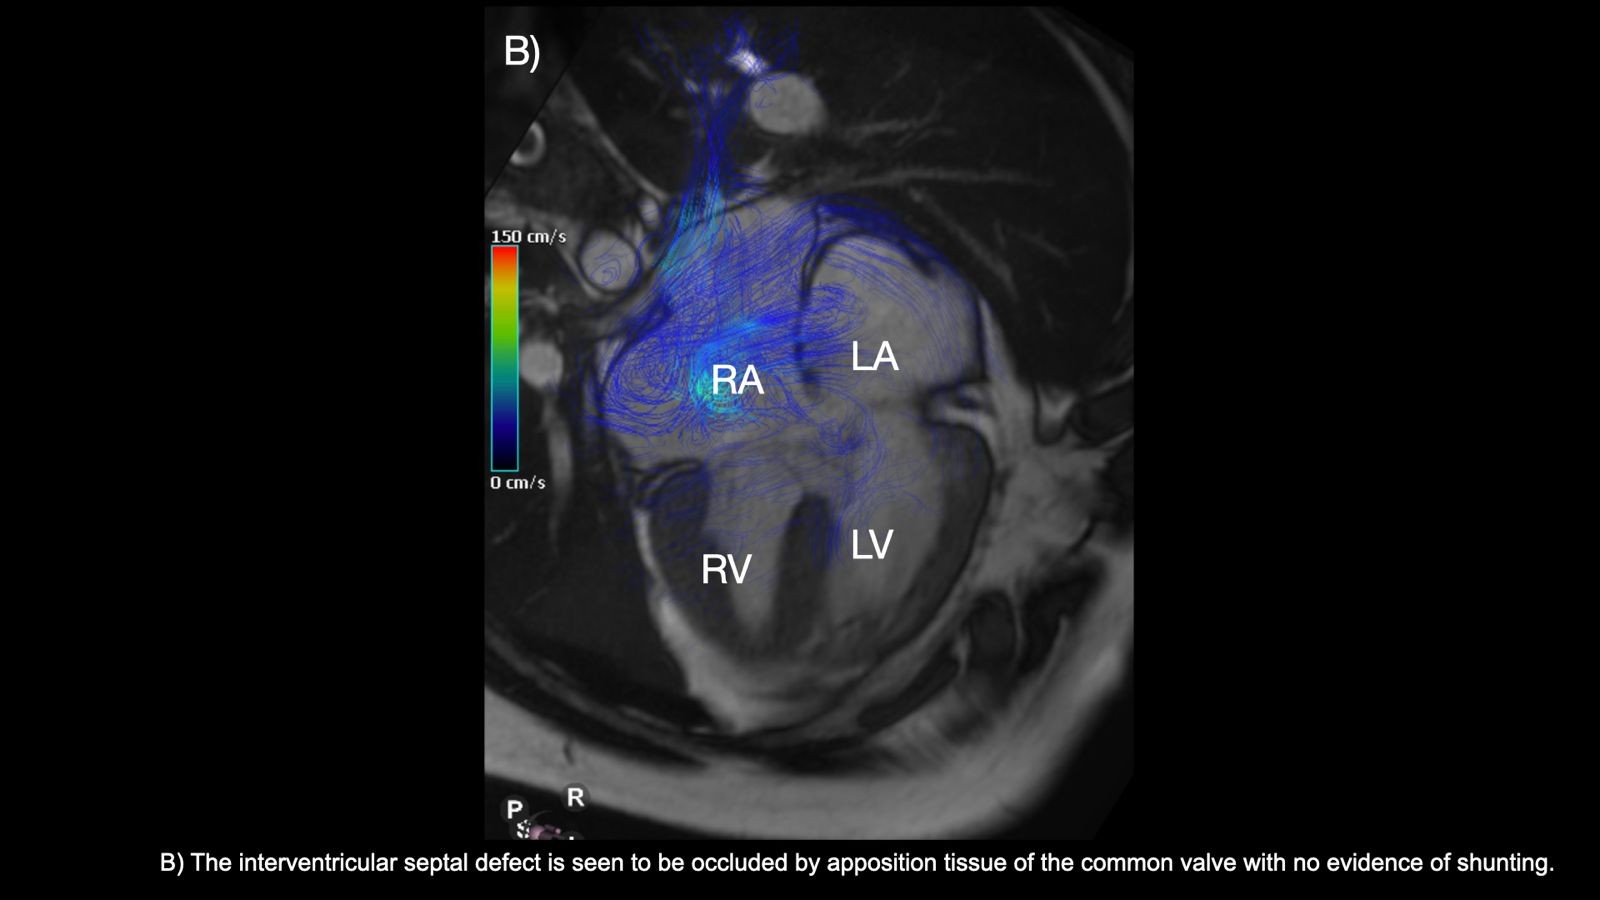

Cardiac Magnetic Resonance (CMR) was performed showing an AVSD-transitional type, with a common AV valve with severe regurgitation of the right portion. Also a ostium-primum ASD and a large VSD almost occluded with subvalvular tissue of the common valve, and dilation of the trunk and branches of the pulmonary artery. 4D flow was an excellent tool for evaluation of the shunt at all levels and helped to identify the flow dynamics in this complex congenital heart disease.

Cardiac Magnetic Resonance (CMR) was performed showing an AVSD-transitional type, with a common AV valve with severe regurgitation of the right portion. Also a ostium-primum ASD and a large VSD almost occluded with subvalvular tissue of the common valve, and dilation of the trunk and branches of the pulmonary artery. 4D flow was an excellent tool for evaluation of the shunt at all levels and helped to identify the flow dynamics in this complex congenital heart disease.

4D flow not only indicated that the VSD was partially occluded by subvalvular tissue, but also demostrated the presence of residual flow through it, which would have gone unnoticed during the echocardiogram. It also allows the measurement of the regurgitant volume of the left AV valve, and mapping of the flow jet shunt through the ASD and residual VSD, revealing a bidirectional shunt. Without it, the transitional AVSD might have been misclassified as “partial” AVSD.